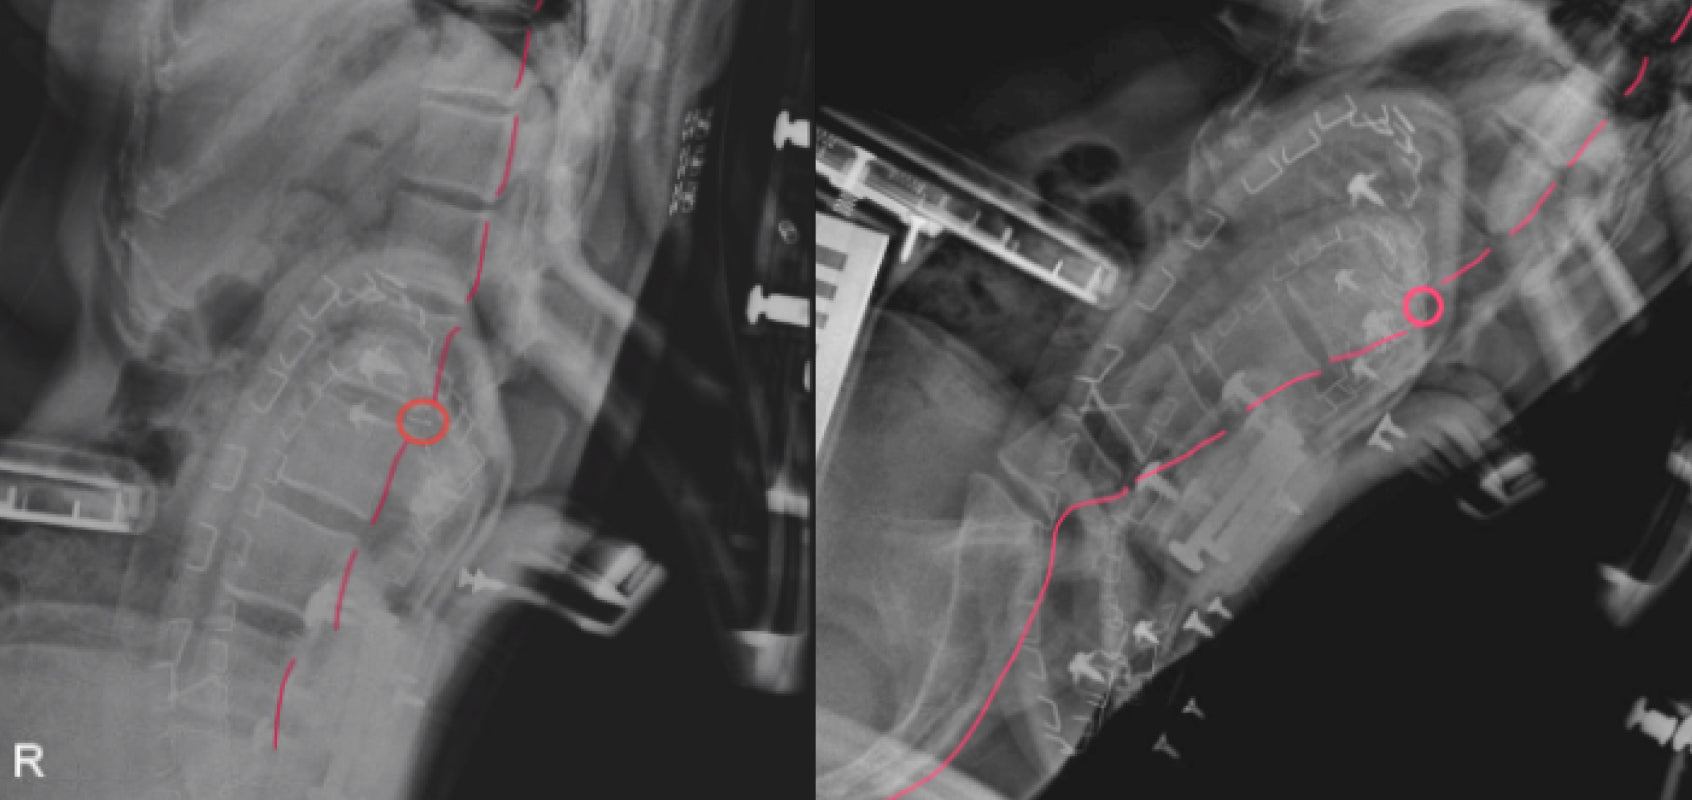

腰部を強く支える設計のチェアは使用者の体型によっては、背中のラインと合わない場合があります。

その結果、背骨のラインが崩れ、一部に負担がかかりやすくなることが確認されています。

*情報源: LiberNovo社内ラボ